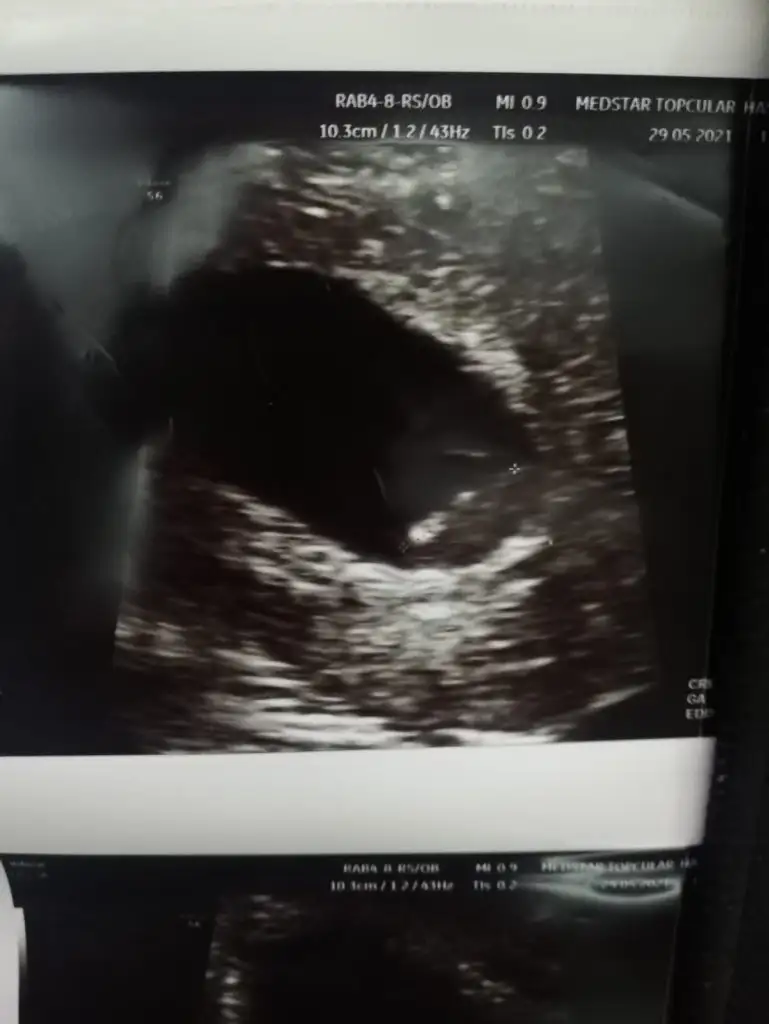

Benimkinde tahmin edermisin

Eklentiler

• IMG-20210613-WA0002.webp

IMG-20210613-WA0002.webp

18,7 KB · Görüntüleme: 71